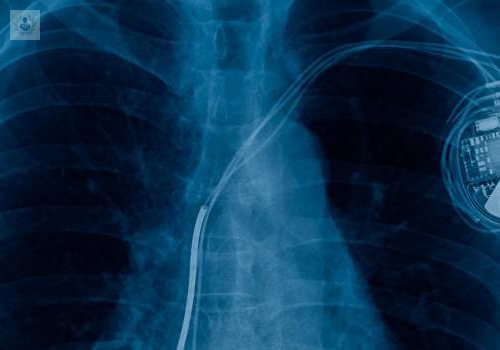

¿En qué consiste la implantación de un Desfibrilador Interno?

Un Desfibrilador Interno es un dispositivo, también conocido como Desfibrilador Automático Implantable (DAI), que ayuda a mejorar la vida de muchos pacientes con problemas de corazón